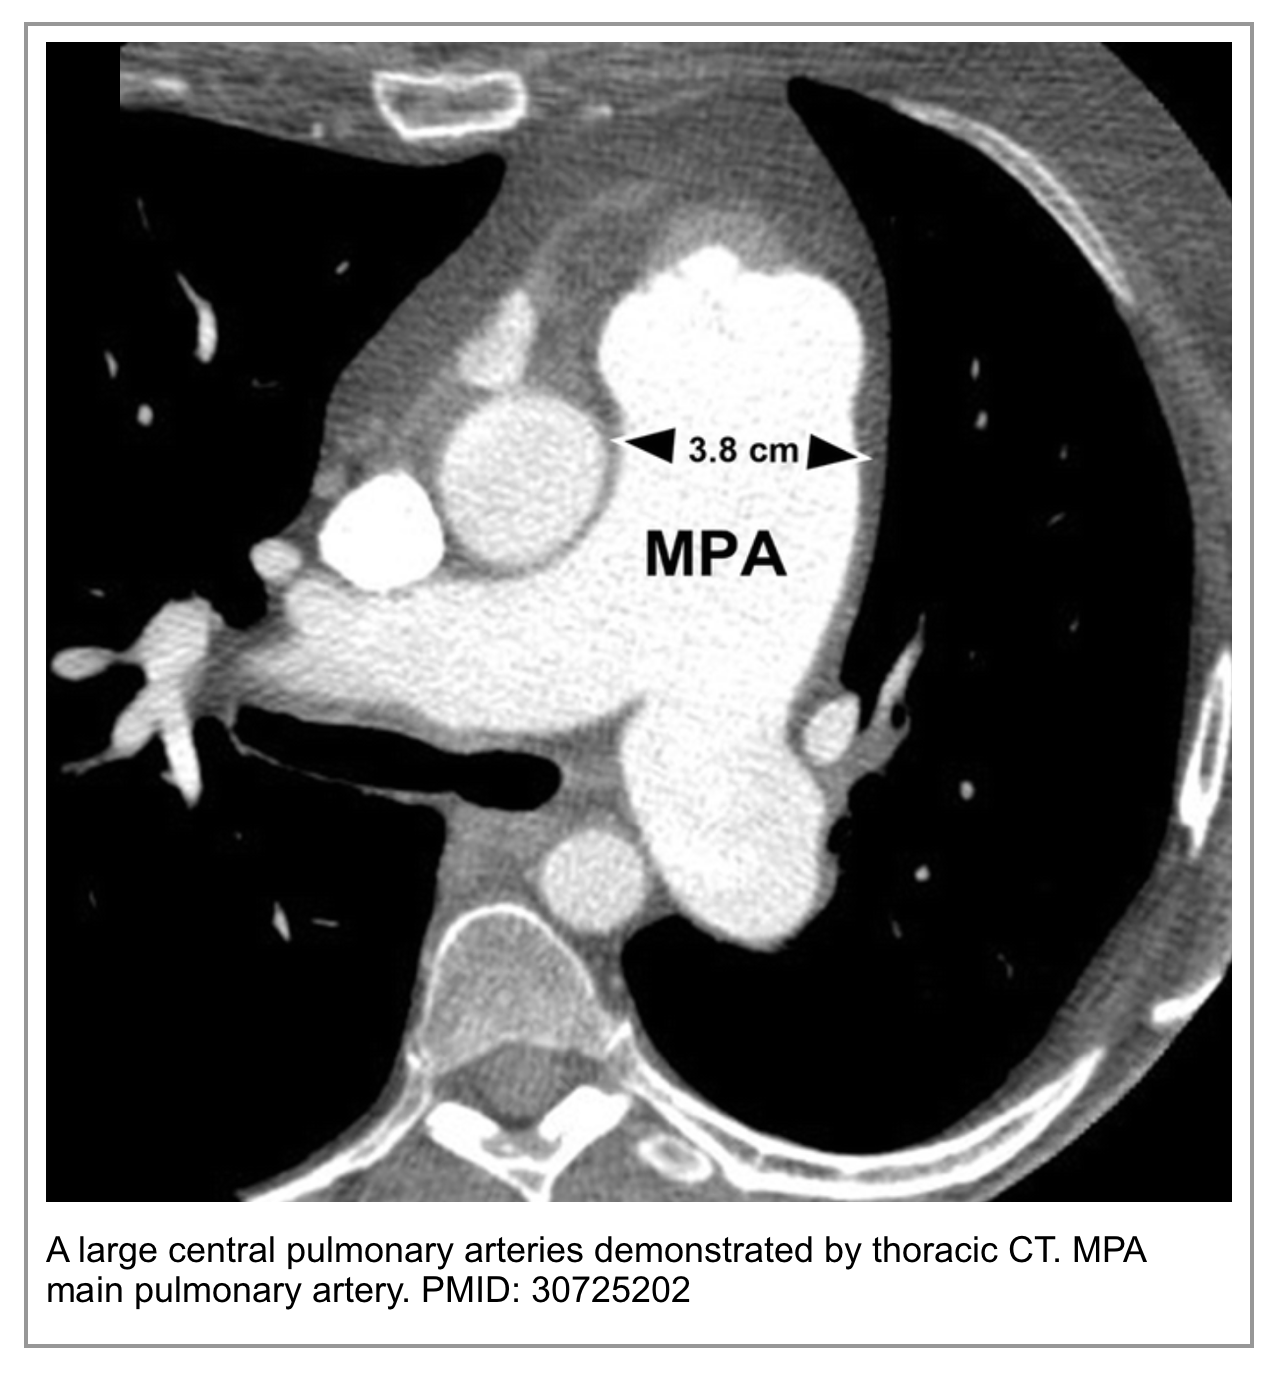

◾️Main Pulmonary Artery (MPA) Diameter

- MPA dilation is a hallmark of chronic pulmonary hypertension. A diameter of ≥29 mm (or > the diameter of the ascending aorta at the same level) is a key supporting feature.

- This dilation develops over time due to sustained high pressure in the pulmonary arterial system. Its presence strongly argues against a first, isolated acute PE.